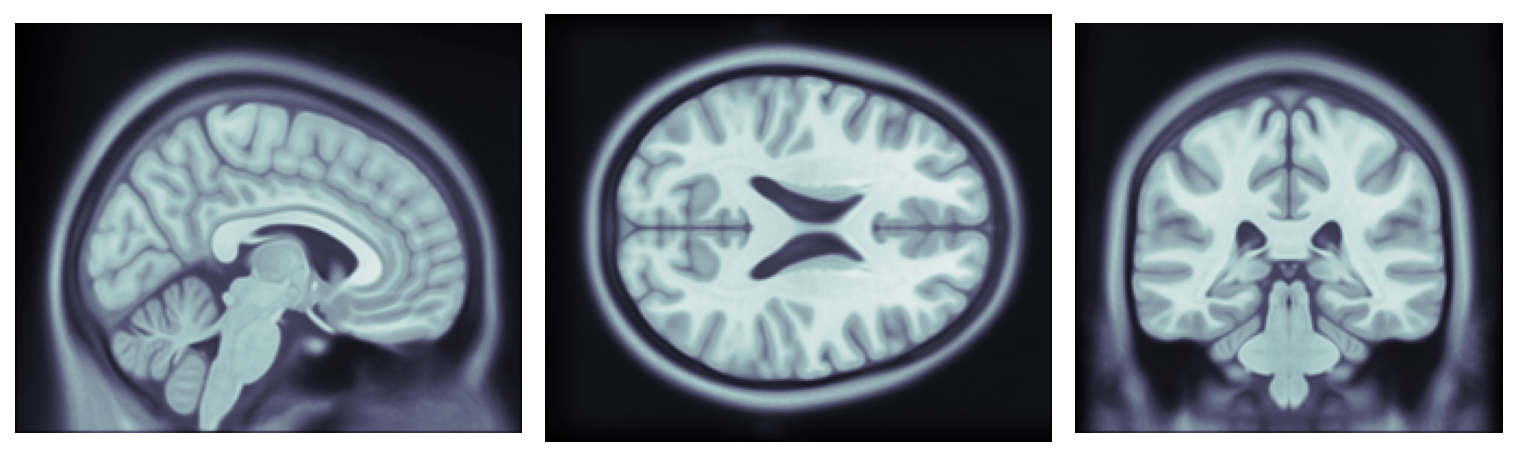

Each of the 50 images was transformed aiming to maximize its similarity with a reference image. The reference image is the MNI ICBM 152111Available at http://nist.mni.mcgill.ca/?p=858, a nonlinear symmetric atlas with 1×1×1 mmtimestimestimes111mm1\text{\times}1\text{\times}1\text{\,}\mathrm{m}\mathrm{m} resolution (Grabner et al. 2006; Fonov et al. 2009). The reference image is presented in Figure 2. Using an average head geometry as reference avoids having to choose one of the images in the dataset as reference, eliminating the possibility of choosing as a reference an individual with any abnormal geometric feature. Each transformation is performed in two stages, first a rigid transformation to roughly align the geometries, followed by an affine transformation.

Refer to caption

Figure 2: Slices of the reference image MNI ICBM 152.

The normalization process assumes the heads have similar shapes and proportions. Therefore, the atlas represents a head with size and proportions similar to the reference head used for the normalization. If necessary, the resulting atlas can be transformed to accommodate other geometries, for example when the geometry of the head of the patient is available or if an average head model is preferred. This procedure will be described in Section 3.3